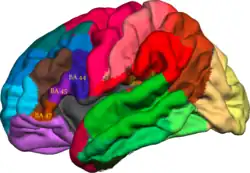

The ventrolateral prefrontal cortex (VLPFC) is a section of the prefrontal cortex located on the inferior frontal gyrus, bounded superiorly by the inferior frontal sulcus and inferiorly by the lateral sulcus. It is attributed to the anatomical structures of Brodmann's area (BA) 47, 45 and 44 (considered the subregions of the VLPFC – the anterior, mid and posterior subregions).

The whole right VLPFC is active during motor inhibition, having a critical role, meaning when a person is walking and suddenly stops, the VLPFC activates to stop or override the motor activity in the cortex. The right posterior VLPFC (BA 44) is active during the updating of action plans. The right middle VLPFC (BA 45) responds to decision uncertainty (presumably in right-handed individuals).[4]